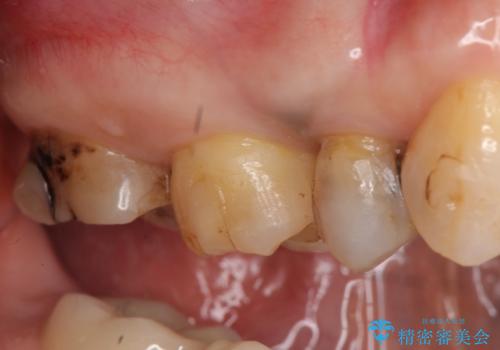

診査の結果痛みの原因は右上7番目だったため、古い樹脂と虫歯を除去後、オールセラミッククラウンによる補綴を行いました。

また右上5、6番目の歯も治療を希望されたため、オールセラミッククラウンによる補綴を行いました。

今回用いたオールセラミッククラウンはジルコニアフレームという白い素材の上にセラミックを盛っているため、審美性が非常に高いのが特徴です。

また、ジルコニアは人工ダイヤモンドの材料にも使われているほど高い強度を持っており、そのためオールセラミッククラウンは審美性だけでなく、奥歯やブリッジの補綴も可能とするクラウンです。